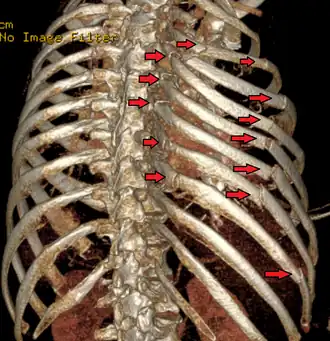

| Uma reconstrução 3D de uma tomografia computadorizada mostrando um tórax instável. As setas marcam as fraturas das costelas. | |

Ocorre quando múltiplas costelas adjacentes são quebradas em vários lugares, separando um segmento, de modo que uma parte da parede torácica se move de forma independente. O número de costelas que devem ser quebradas varia de acordo com diferentes definições: algumas fontes dizem que pelo menos duas costelas adjacentes estão quebradas em pelo menos dois lugares,[1] algumas requerem três ou mais costelas em dois ou mais lugares.[2] O segmento instável se move na direção oposta ao resto da parede torácica: devido à pressão ambiente em comparação com a pressão dentro dos pulmões, ele entra enquanto o resto do tórax se move para fora e vice-versa. Esta chamada "respiração paradoxal"[3] é dolorosa e aumenta o trabalho envolvido na respiração.

O tórax instável normalmente ocorre quando três ou mais costelas adjacentes são fraturadas em dois ou mais locais, permitindo que esse segmento da parede torácica se desloque e se mova independentemente do resto da parede torácica. O tórax instável também pode ocorrer quando as costelas são fraturadas proximalmente em conjunto com a desarticulação das cartilagens costais distalmente. Para que a condição ocorra, geralmente deve haver uma força significativa aplicada sobre uma grande superfície do tórax para criar múltiplas fraturas de costelas anteriores e posteriores. Lesões por capotamento e esmagamento geralmente quebram as costelas em apenas um ponto, enquanto para que o tórax instável ocorra é necessário um impacto significativo, quebrando as costelas em dois ou mais lugares.[15] Isso pode ser causado por acidentes violentos, como as colisões de veículos mencionadas acima ou quedas significativas. Nos idosos, pode ser causada pela deterioração óssea, embora rara. Em crianças, a maioria das lesões torácicas instáveis resulta de traumas comuns de força contundente ou doenças ósseas metabólicas, incluindo um grupo de doenças genéticas conhecidas como osteogênese imperfeita.[16]